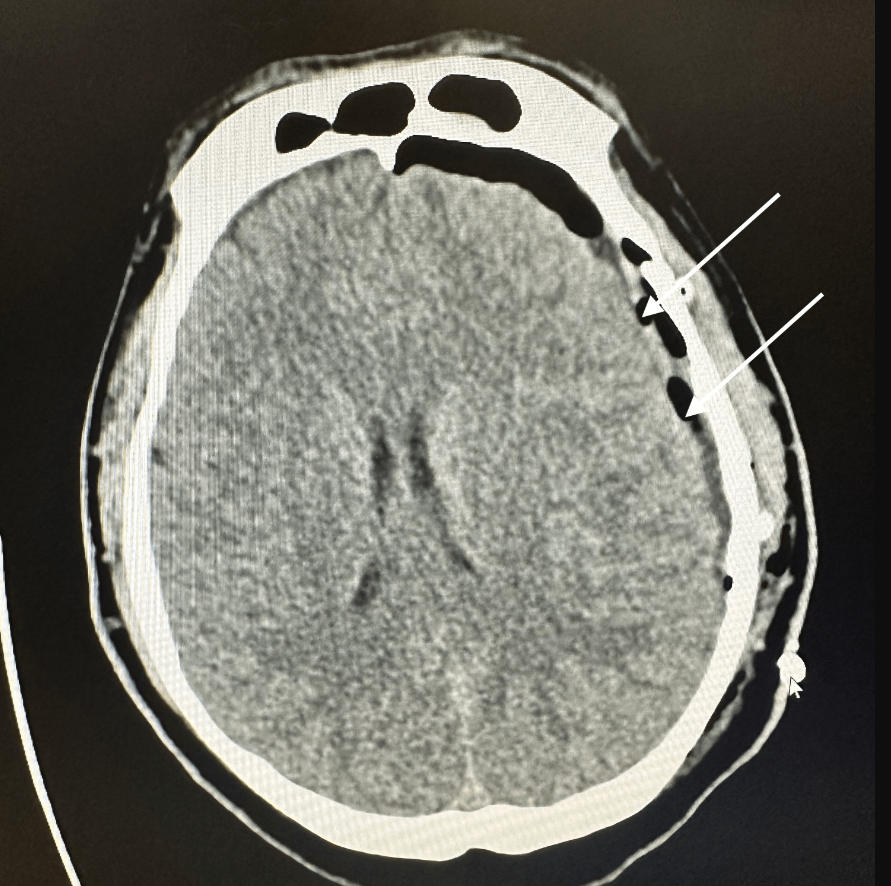

29일 의학 학술지 Cureus에는 헬스장에서 격렬한 운동을 하던 중 뇌에 피가 고이는 ‘비외상성(자발성) 경막하혈종(Spontaneous Subdural Hematoma, SDH)’ 진단을 받은 미국인 남성의 사례가 소개됐다. 그는 과거 병력도 없고, 머리에 충격을 입은 적도 없던 전형적인 ‘건강한 젊은 남성’이었다.

경막하혈종은 보통 외상에 의해 발생하는 경우가 많다. 그러나 이 환자는 외부 충격을 받은 적이 없었고, 추가 검사에서도 혈관 기형이나 동정맥 이상은 발견되지 않았다.

이에 의료진은 비외상성 경막하혈종을 진단했고, 개두술을 통한 혈종 제거 수술을 권고했다. 그러나 환자는 초기에는 이를 거부하고 보존적 치료를 선택했다.

이후 증상이 악화되면서 그는 결국 수술을 받았고, 수술 5일 후 퇴원할 수 있었다.

의료진은 “환자가 운동 전 탈수 상태였고, 운동 직전에 고카페인 음료를 마셨다”며 “이러한 저수분 상태와 카페인, 격렬한 운동이 복합적으로 작용해 정맥압을 높이고 출혈 가능성을 높였을 수 있다”고 설명했다.